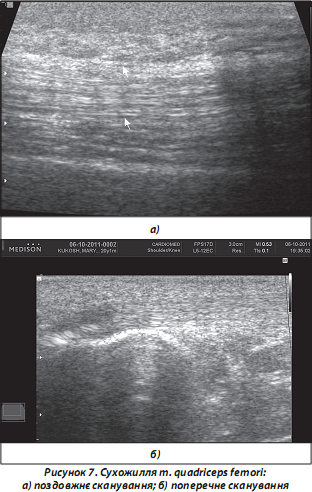

7. Сухожилля при проведенні УЗД добре візуалізуються як при поздовжніх, так і поперечних скануваннях, у вигляді лінійно розташованих фібрилярних гіпер-/гіпоехогенних структур із досить чіткими контурами та візуалізацією волокнистої структури (рис. 7).

Деякі сухожилля (m. biceps brachii, m. quadriceps femori тощо) оточені гіпоехогенною зоною хало [Зубарев А.В., 2002], що відображає наявність СО, яка містить невелику кількість рідини навіть у нормі.

Інші сухожилля (наприклад, ахіллове), не мають СО, оточені сполучною тканиною (СТ), що формує навколосухожильний простір; у місці прикріплення завжди формують сухожильні сумки (бурси).